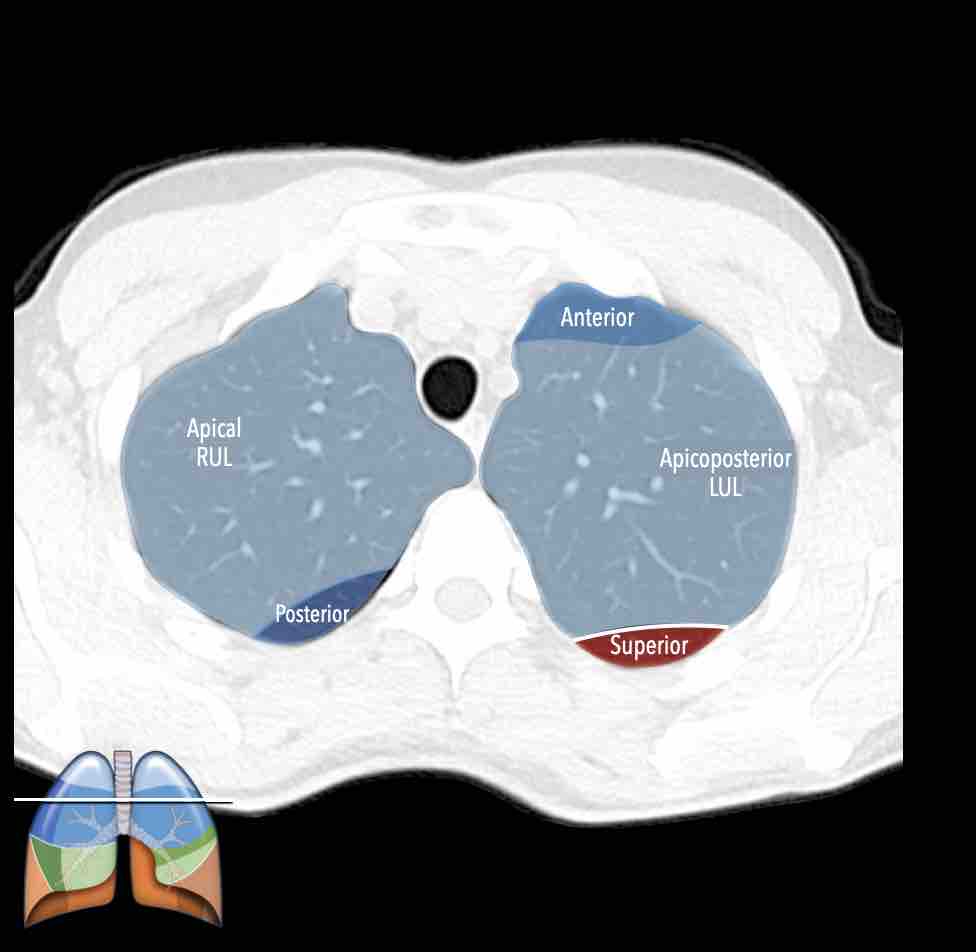

Các phân thùy phổi trên CT

Cuộn qua các hình ảnh để quan sát cách phổi được phân chia thành các phân thùy.